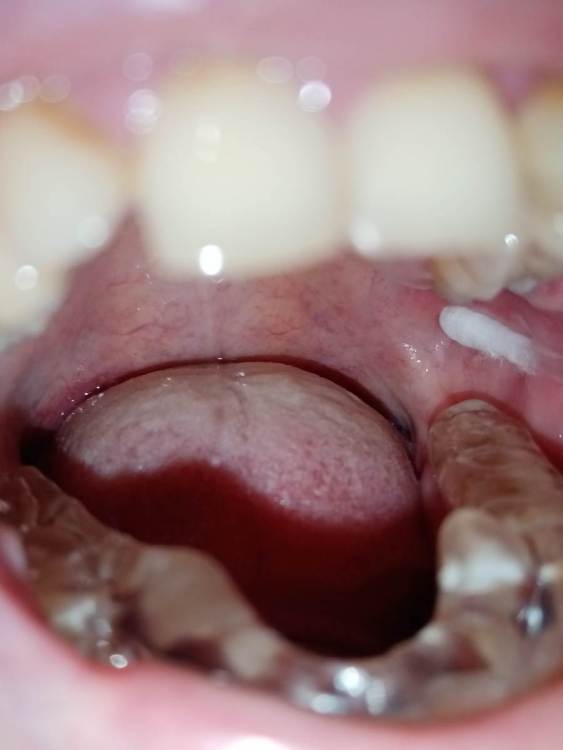

СмирноваД Опубликовано 29 июня, 2023 Поделиться Опубликовано 29 июня, 2023 Уважаемые стоматологи. Прошу Вашей помощи в поиске проблемы. Зуб удалили 2 года назад, но покоя там слизистая не дает. Болит, Разговаривать не дает вообще. Как буд-то там все пришили, и щеку и тяж со стороны горла. Какая-то шишка растет в конце верхней челюсти и как-будто давит там. Срослось оно вот таким образом "V"(со слов врача). Дергает щеку сильно , как-будто она прям пытается оторваться оттуда. и при наклоне головы прям в это место отдает. Со стороны горла тяж пришитый прям лоскутом к челюсти со стороны языка, трется об язык и тянет так сильно, что не дает разговаривать вообще, больно любые напряжения(разговаривать, глотать, пить,смеяться, и т.д.) прям чувствую как оно там все двигается, как нахождении чего-то инородного. Постоянно там все полощу, держу воду, потому что жжёт сильно. И доходит до рвотного рефлекса. Со стороны щеки,за зубом 4.7 корман. Пища попадает , и вытащить ее проблематично. Постоянно ощущение воспаления и лазию туда языком отодвигаю этот тяж, засовываю туда ватный диск, что бы просто снять напряжение и в этот момент могут быть такие жутки спазмы, что замираешь от боли. До трясучки и панических атак уже. Прикусываю там все, при чом даже с шиной (сплинт), щека лезет между зубов, приходится щеку вытаскивать.Шину ношу уже 10 месяцев, а толку нет. Рефлекторно, стараешься не двигать просто правой стороной вообще. Гнатолог , который делал шину, сказал, что нужно убирать рубцы, они все тянут. Но когда дошло дело до хирурга, хирург развел руками и сказал жить так, т.к. он ни чего сделать не может. Мало того у меня проблемы с суставом. а из-за этого напряжения на столько хуже, что к вечеру ни то что бы разговаривать, я и глотать слюну не могу. Сустав у меня теперь болит постоянно от напряжения, жуткие спазмы по всей голове, челюсти, до горла болит, с переходом на шею. При чом все врачи видят эти рубцы, что все прикусываю, трогают и мне больно, но говорят все по разному : один- надо искать, другой - там воспаление, третий- прикус, четвертый -как вы себе представляете это, это нужно было убирать сразу, пятый-сустав. Просто как идти к ортодонту с такими болями? И так же искала врача по пластике, но безрезультатно. На кт и снимках нет ни чего. Помогите, пожалуйста, хоть как-то разобраться. 230310_183333.rar Ссылка на комментарий

annda Опубликовано 27 июля, 2023 Поделиться Опубликовано 27 июля, 2023 (изменено) Нельзя на ортодонтию идти в таком состоянии. Начните с банальной рутинной ежедневной самокоррекции хотя бы-пилатес,йога, Фельденкрайз и прочие подобные штуки. Единственные рубцы,которые у вас есть-это «линия Альба»,,следы прикусывания щек зубами.К месту удаления это не имеет никакого отношения, а к бруксизму -самое прямое. Изменено 27 июля, 2023 пользователем annda Ссылка на комментарий

Bier Опубликовано 16 августа, 2023 Поделиться Опубликовано 16 августа, 2023 я вижу рубец на щеке, вы накусали его, ну если он мешает можно его отрезать. Но по источнику боли соглашусь с Анной. Ссылка на комментарий